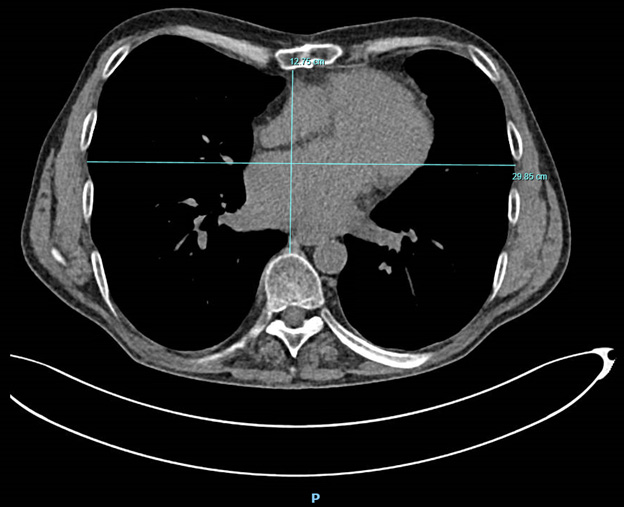

on their Haller index (HI) [14]. In the axial plane, the HI was calculated as the

maximum transverse diameter of the chest wall divided by the minimum anterior

posterior distance between the sternum and vertebrae (Fig. 1). Group 1 was

defined as a normal chest with a HI

Fig. 1.An axial computed tomography (CT) scan of a 58-year-old male patient, before left ventricular assist device (LVAD) implantation. The maximal transverse diameter is 29.85 centimeters (cm) and minimum anterior posterior distance is 12.75 cm. Haller index; 29.85/12.75 = 2.34, categorized as Haller index 2, mild pectus excavatum. P, posterior side of the patient.